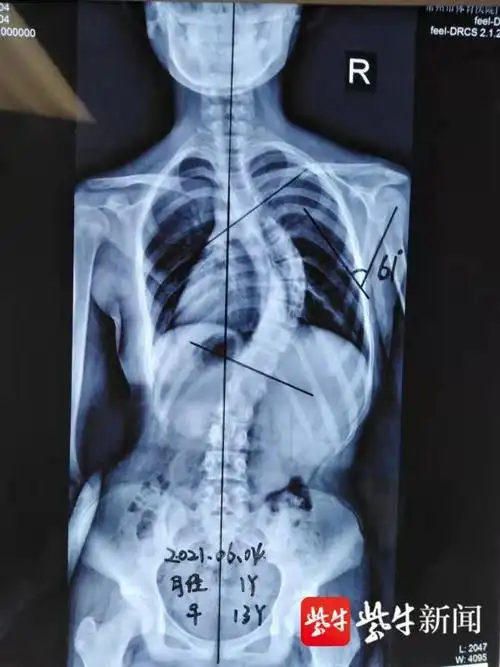

13岁女生头像可爱 甜美